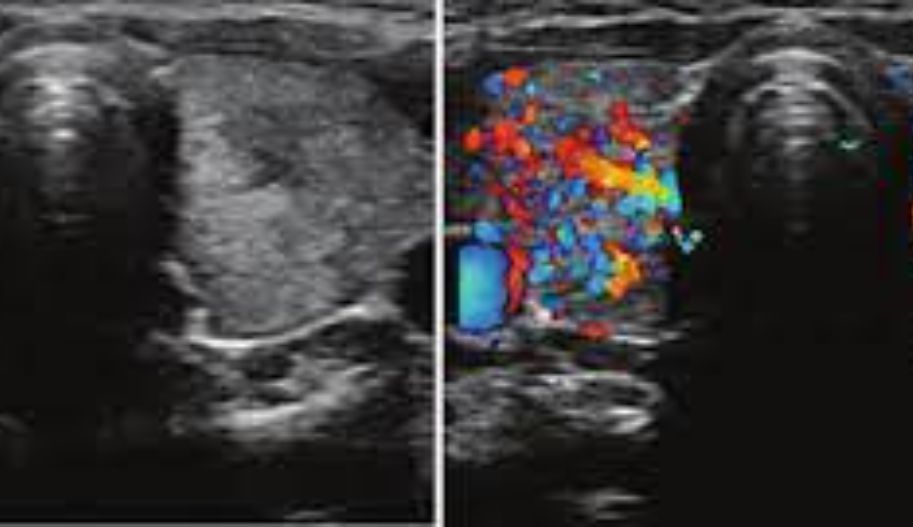

Carotid Vertebral Artery Color Doppler Ultrasound

Carotid vertebral artery color Doppler ultrasound is an excellent screening tool to assess whether carotid artery stenosis is hemodynamically significant. It is a crucial imaging method to be performed before angioplasty, endarterectomy, or stent placement.

A general assessment to determine the extent of atherosclerotic disease and the localization of carotid artery branches is essential before focusing on a specific arterial segment. This initial analysis is performed in the transverse plane, starting from the proximal common carotid artery (CCA) and proceeding to the bifurcation level, then moving on to the internal and external carotid arteries (ICA and ECA, respectively). The ECA typically appears smaller in diameter and more medial and anterior, feeding the face, while the ICA tends to be larger and positioned posterior and lateral compared to the ECA. The CCA, ECA, and ICA are then scanned longitudinally to investigate the presence of plaque formation.